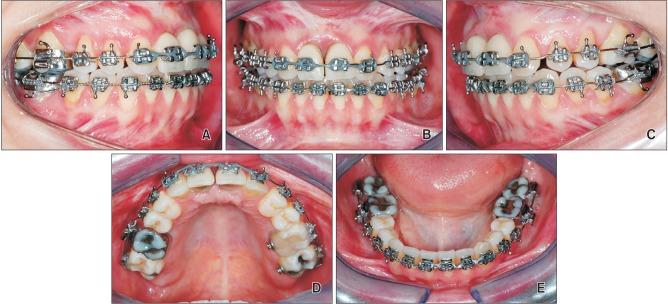

The aim of this clinical report is to describe the complex treatment of an adult Class III malocclusion patient who was disappointed with the outcome of a previous oral rehabilitation. Interdisciplinary treatment planning was performed with a primary indication for implant removal because of marginal bone loss and gingival recession, followed by orthodontic and surgical procedures to correct the esthetics and skeletal malocclusion. The comprehensive treatment approach included: (1) implant removal in the area of the central incisors; (2) combined orthodontic decompensation with mesial displacement and forced extrusion of the lateral incisors; (3) extraction of the lateral incisors and placement of new implants corresponding to the central incisors, which received provisional crowns; (4) orthognathic surgery for maxillary advancement to improve occlusal and facial relationships; and finally, (5) orthodontic refinement followed by definitive prosthetic rehabilitation of the maxillary central incisors and reshaping of the adjacent teeth. At the three-year follow-up, clinical and radiographic examinations showed successful replacement of the central incisors and improved skeletal and esthetic appearances. Moreover, a Class II molar relationship was obtained with an ideal overbite, overjet, and intercuspation. In conclusion, we report the successful esthetic anterior rehabilitation of a complex case in which interdisciplinary treatment planning improved facial harmony, provided gingival architecture with sufficient width and thickness, and improved smile esthetics, resulting in enhanced patient comfort and satisfaction. This clinical case report might be useful to improve facial esthetics and occlusion in patients with dentoalveolar and skeletal defects.

本临床报告旨在描述一名成年III类错牙合患者的复杂治疗过程,该患者对先前口腔修复的结果不满意。由于边缘骨丢失和牙龈退缩,进行了跨学科治疗计划,主要指征是移除种植体,随后进行正畸和外科手术以纠正美观和骨骼错牙合问题。综合治疗方法包括:(1) 移除中切牙区域的种植体;(2) 联合正畸代偿,使侧切牙向近中移位并强行萌出;(3) 拔除侧切牙并在对应中切牙位置植入新的种植体,新种植体安装临时冠;(4) 进行正颌手术使上颌前徙,以改善咬合和面部关系;最后,(5) 正畸精细调整,随后对上颌中切牙进行最终的修复治疗并对相邻牙齿进行塑形。在三年随访时,临床和影像学检查显示中切牙成功替换,骨骼和美观外观均得到改善。此外,获得了II类磨牙关系,覆牙合、覆盖和牙尖交错关系理想。总之,我们报告了一例复杂病例的成功美学上前牙修复,其中跨学科治疗计划改善了面部和谐,为牙龈结构提供了足够的宽度和厚度,改善了微笑美学,提高了患者的舒适度和满意度。本临床病例报告可能有助于改善牙列和骨骼缺陷患者的面部美学和咬合情况。